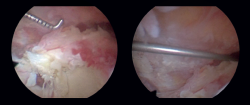

La técnica quirúrgica consistió en realizar en todos los pacientes una artroscopia de hombro con posición en silla de playa. Se utilizó profilaxis antibiótica pre- y posquirúrgica con cefazolina. Se realizaron los portales posterior y lateral subacromial, se hizo un desbridamiento de la bursa subacromial y la tenotomía de la porción larga del bíceps mediante el uso de un vaporizador en todos ellos. En el grupo del balón subacromial asociado (balón InSpace® de Stryker, Michigan, USA), se realizó antes de su implantación la medida del tamaño de este de entre los 3 tamaños posibles, midiendo aproximadamente desde 1 cm medial al borde glenoideo hasta la región lateral del troquíter. Posteriormente, se introdujo el implante a través del portal lateral y se rellenó con suero salino estéril hasta el límite recomendado según la técnica quirúrgica (desde 9 a 24 cm3 en función del tamaño seleccionado del balón). Posteriormente, se liberó el balón tras comprobar previamente su correcta posición por encima de la glena y 2 cm sobre el muñón del tendón del manguito rotador y su estabilidad observando que no interfiere con las maniobras pasivas de rango de movimiento del hombro del paciente (Figuras 1 y 2).

Figura 2. Proceso de colocación del balón subacromial por vía artroscópica a través del portal lateral subacromial.